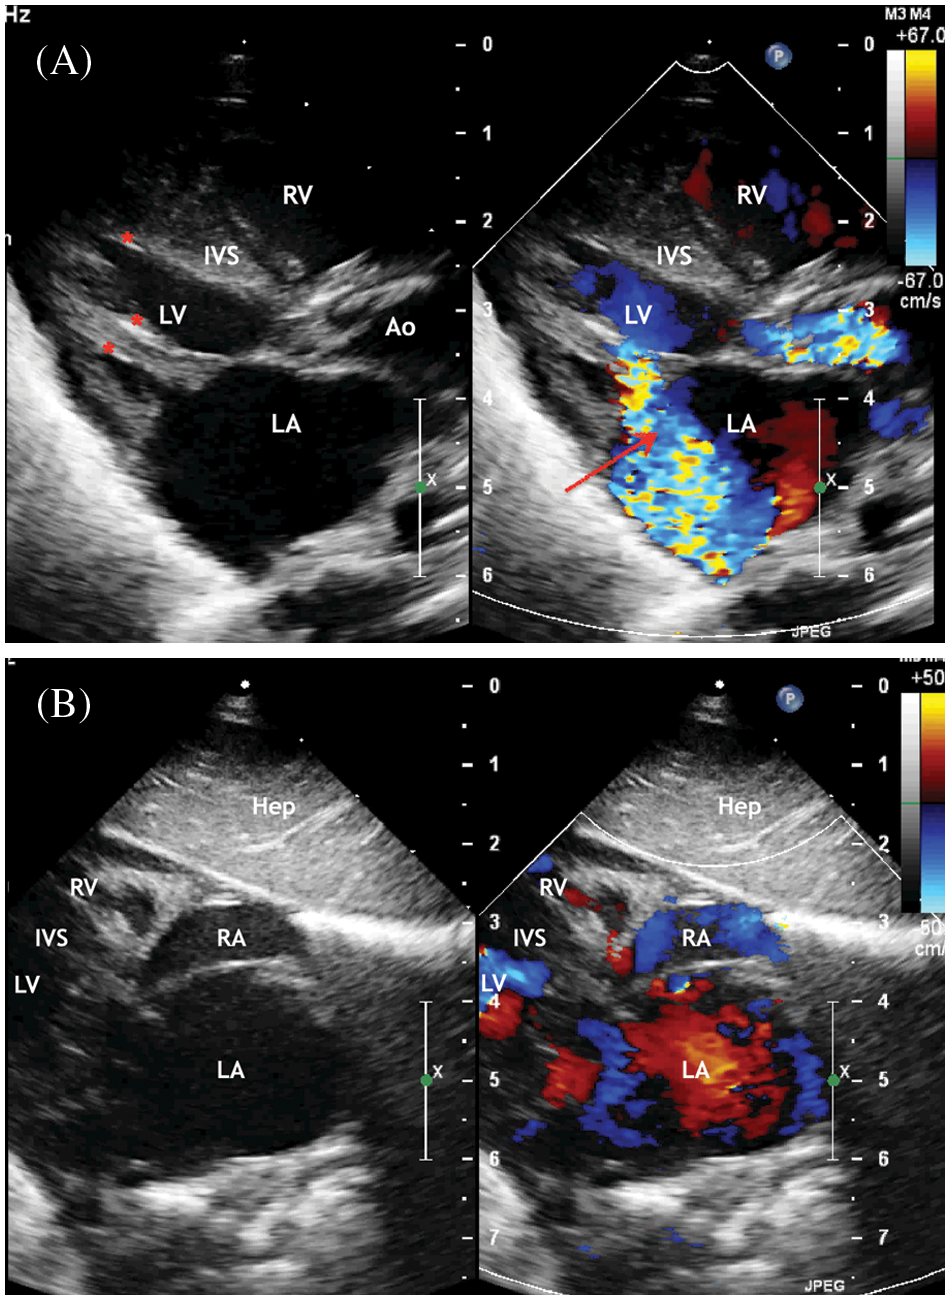

Figure 1: ECHO. (A) Parasternal long-axis view. Systole phase of the LV. LV myocardial hypertrophy, turbulent flow through the aortic valve is visualized. Aortic valve annulus diameter 6 mm but opening diameter 2.1 mm. Severe mitral regurgitation (marked with an arrow) with an enlarged of the left atrium. Areas of fibroelastosis of the LV (marked with an asterisk). (B) Subcostal view. Enlarged of the left atrium. Displacement of the interatrial septum to the right

Abbreviation: RV, the right ventricle; LV, the left ventricle; LA, the left atrium; RA, the right atrium; Ao, the ascending aorta. IVS, the interventricular septum; Hep, the liver.